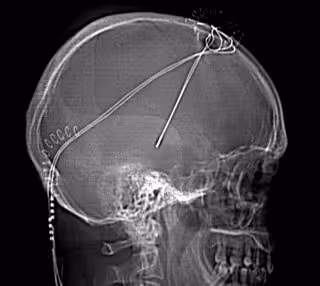

"Hoy día se pueden llegar a ver en la resonancia magnética, con extraordinaria precisión, los núcleos neuronales implicados en esta enfermedad. Se puede acceder a ellos con muy baja o nula morbilidad o mortalidad. Y se puede colocar en estos núcleos un dispositivo muy complejo que consiste en un electrodo a través del cual se manda un estímulo eléctrico que regula el funcionamiento de estos núcleos. Es similar al marcapasos cardiaco, en que queda todo por dentro de la piel, solo que el electrodo está situado a nivel cerebral", ha explicado García de Sola.

Como resultado, el paciente queda sin temblor y con una disminución muy marcada de la rigidez en brazos y piernas en un porcentaje de casos superior al 80 por ciento y sin secuelas quirúrgicas. Esto, además, permite disminuir la cantidad de medicación necesaria para controlar la enfermedad.